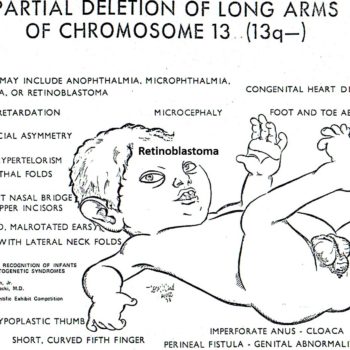

PERSPECTIVE: Clinically (without an autopsy) it is not possible to distinguish agenesis from aplasia of ocular globes (lack of genes or lack of expression). In any case, it is fundamental to remember that the eyes derive from the cerebral frontal lobes. Another perspective is whether there are extra-cephalic concurrent malformations (as in this case).